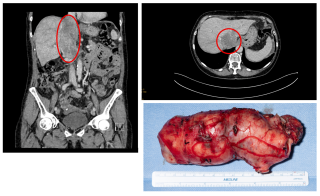

An 82-year-old otherwise healthy man was referred for evaluation of an incidentally detected left adrenal mass. The patient was asymptomatic with no clinical signs of catecholamine excess, hypercortisolism, hyperaldosteronism or B-symptoms. Initial CT scan revealed a 44 × 42 mm lesion, which increased to 50 × 46 mm within three months and suspicious washout characteristics (Figure 1). Endocrinological work-up showed a pathological dexamethasone inhibition test, while metanephrines and aldosterone testing was normal. Tumor markers (AFP, β-HCG) were unremarkable. A hormonally active adrenal adenoma with autonomous cortisol production was suspected.

After discussion at the interdisciplinary tumor board, robotic-assisted adrenalectomy was performed (Figure 2). Complete resection was achieved without complications, the patient was discharged on the third postoperative day.

Histopathological examination showed a Sertoli cell tumor with complete excision and no evidence of local infiltration or malignancy (Figure 3).

Immunohistochemistry showed positivity for CD56, CD99, synaptophysin and partial positivity for SF1, calretinin and inhibin. Chromogranin A and MART1 were negative. Molecular analysis revealed no FOXL2 or DICER1 mutations. Postoperatively, hydrocortisone substitution was initiated due to submaximal cortisol response in ACTH stimulation testing. At six-month follow-up, CT imaging showed no recurrence or metastases and tumor markers remained normal.